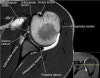

- Axial section

1) Anterior & posterior labrum

2) Subscapularis muscle & tendon

3) Biceps long head tendon

4) GH joint cartilage

5) Osseous structure

6) 관절액 있을때 FSE T2 FS에서 Labrum 선명, 관절액 없을때 FSE PD FS에서 Labrum 선명